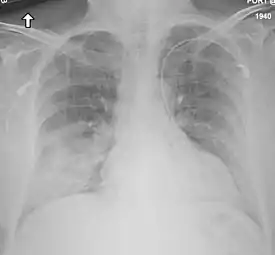

![]() Radiografía de tórax que muestra daño en los pulmones en un paciente con Síndrome respiratorio de Oriente Medio. | ||